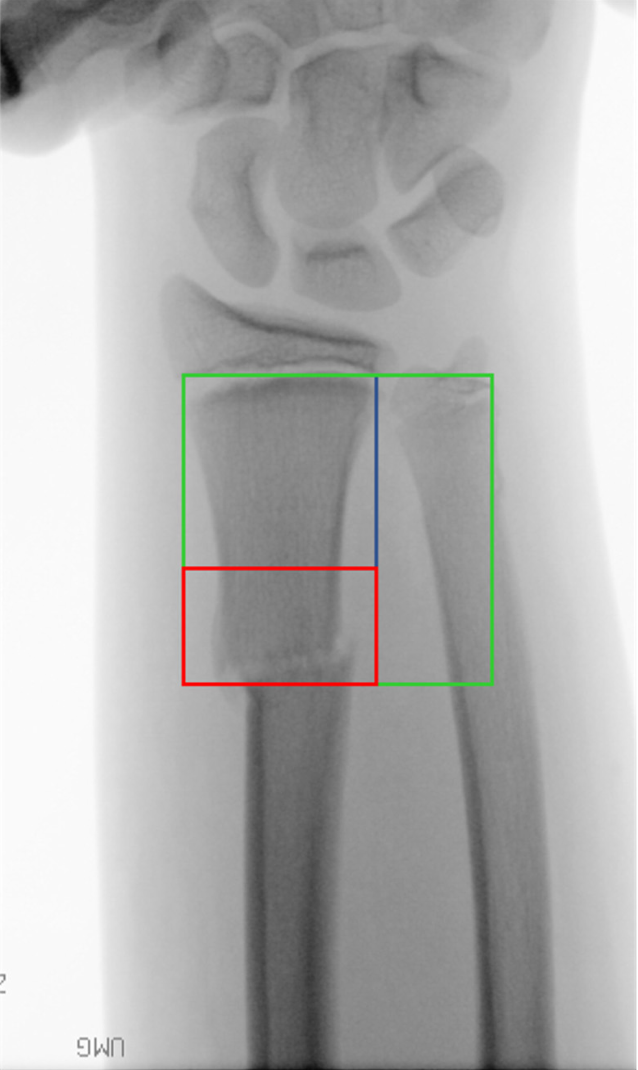

Abb. 1

Definition der Diametaphyse (rot); Subtraktion des Quadrats über der Wachstumsfuge des Radius (blau) vom Quadrat über der Wachstumsfuge von Radius und Ulna (grün)

• Frakturen, die nach Lieber et al. [5] definiert sind (Abb. 1)